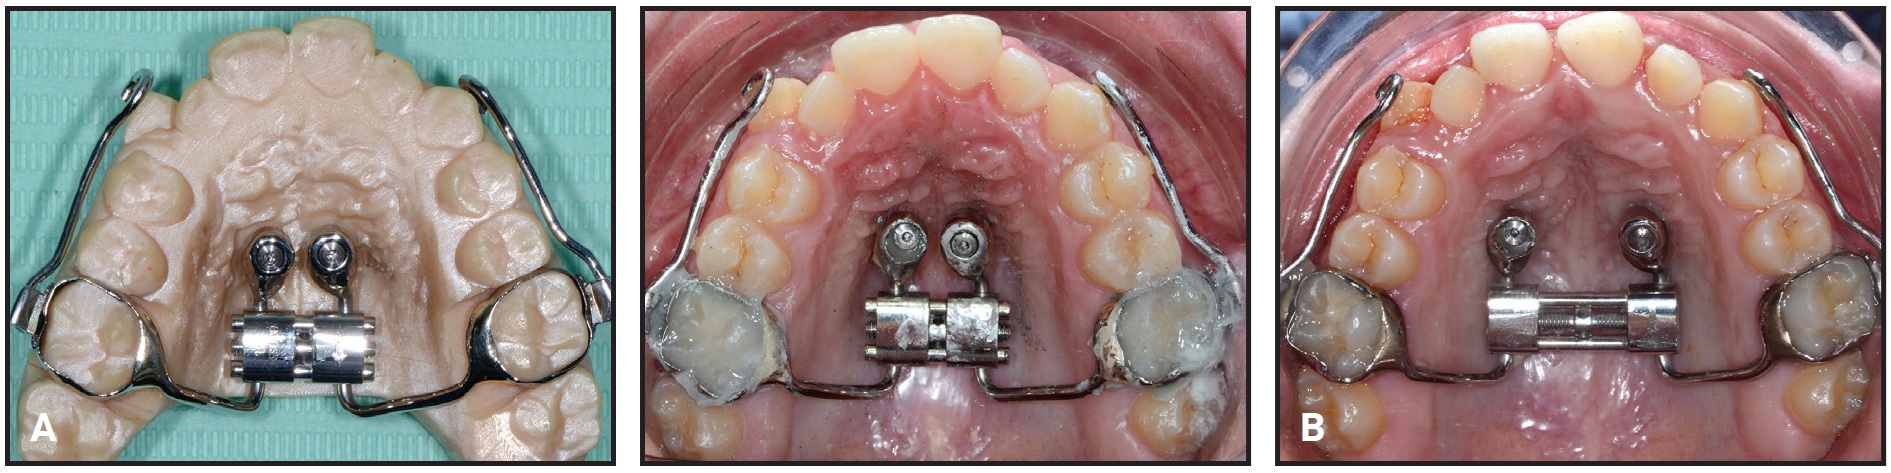

A MAPA surgical guide was digitally designed and 3D-printed to aid in the insertion of 2mm × 11mm Spider Screw K2 Konic miniscrews (Fig. 3).24,25

Next, an h-RPE was fabricated, with buccal arms welded to the first-molar bands for attachment of the facemask (Fig. 4). The anterior palatal arms of the RPE were welded to two metal abutments designed to fit over the miniscrew heads, each affixed with a microscrew. After bonding, the h-RPE was activated until the transverse deficiency was corrected (32 days at one quarter-turn per day).

Fig. 3 Miniscrew placement in palatal vault on three-dimensional digital model.

Fig. 4 A. Hybrid rapid palatal expander (h-RPE) with anterior palatal arms welded to metal abutments over miniscrew heads. B. Skeletal maxillary expansion after 32 days (one quarter-turn per day).

The patient was instructed to wear a protraction facemask 14 hours per day (Fig. 5). A 450g orthopedic force was applied on each side in a downward and forward direction, at an inclination of about 30° to the occlusal plane, until the sagittal dimension had been slightly overcorrected.

After six months of orthopedic treatment, the buccal and posterior arms of the h-RPE were removed, and the facemask was discontinued (Fig. 6).

Fig. 5 Protraction facemask with 450g of orthopedic force applied on each side in downward and forward direction, at about 30° to occlusal plane.

Fig. 6 Buccal and posterior arms of h-RPE removed after six months of orthopedic treatment.